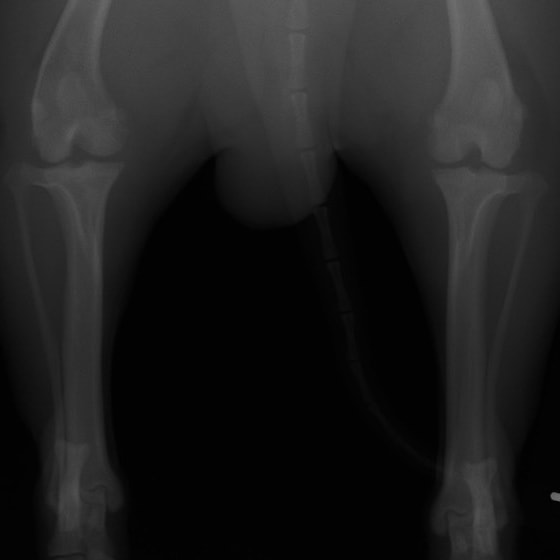

術前正面像

左後肢の挙上を主訴に来院されました。触診にて両関節の前方引き出し兆候、両膝蓋骨の内方脱臼を認めました。関節液検査より免疫介在性多発性関節炎は否定的でした。レントゲン検査にてfat pad signを伴う関節炎が認められたことから、前十字靭帯断裂と膝蓋骨内方脱臼(左GradeⅢ 右GradeⅢ〜IV)併発と診断し、手術を行いました。

手術は片足ずつ行い、両膝とも術中の関節鏡検査にて前十字靭帯の完全断裂と半月板損傷を確認しました。TPLO、半月板切除と滑車溝形成を始めとした膝蓋骨脱臼整復術を実施いたしました。膝蓋骨の安定化を測るために外側支帯を強固に縫合し、内側支帯は切除し縫合せずに開放状態にしています。

術前のTPAは左後肢33.1°右後肢26.8°でしたがTPLO実施により左後肢5.5°右後肢12°に矯正されました。